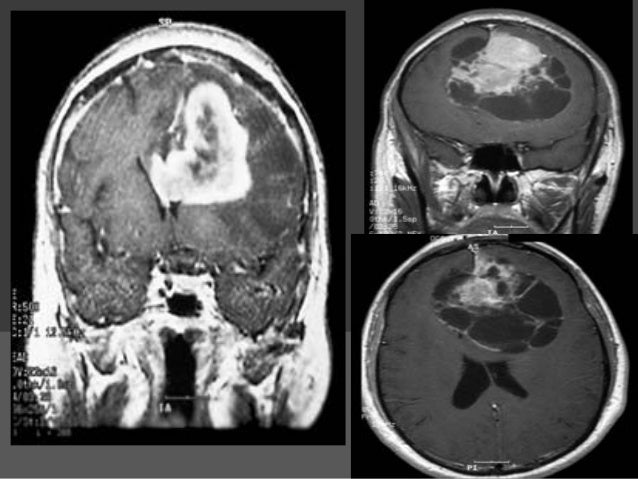

44+ Surgery Brain Tumor Images Pics. Show brain tumor at right parietal lobe of cerebrum. There are two main types of tumors:

This type of imaging test (described in tests for brain and spinal cord tumors in. 638 x 479 jpeg 67 кб. This required six different surgical procedures to be conducted on the patient. It can be benign (noncancerous) or malignant (cancerous).